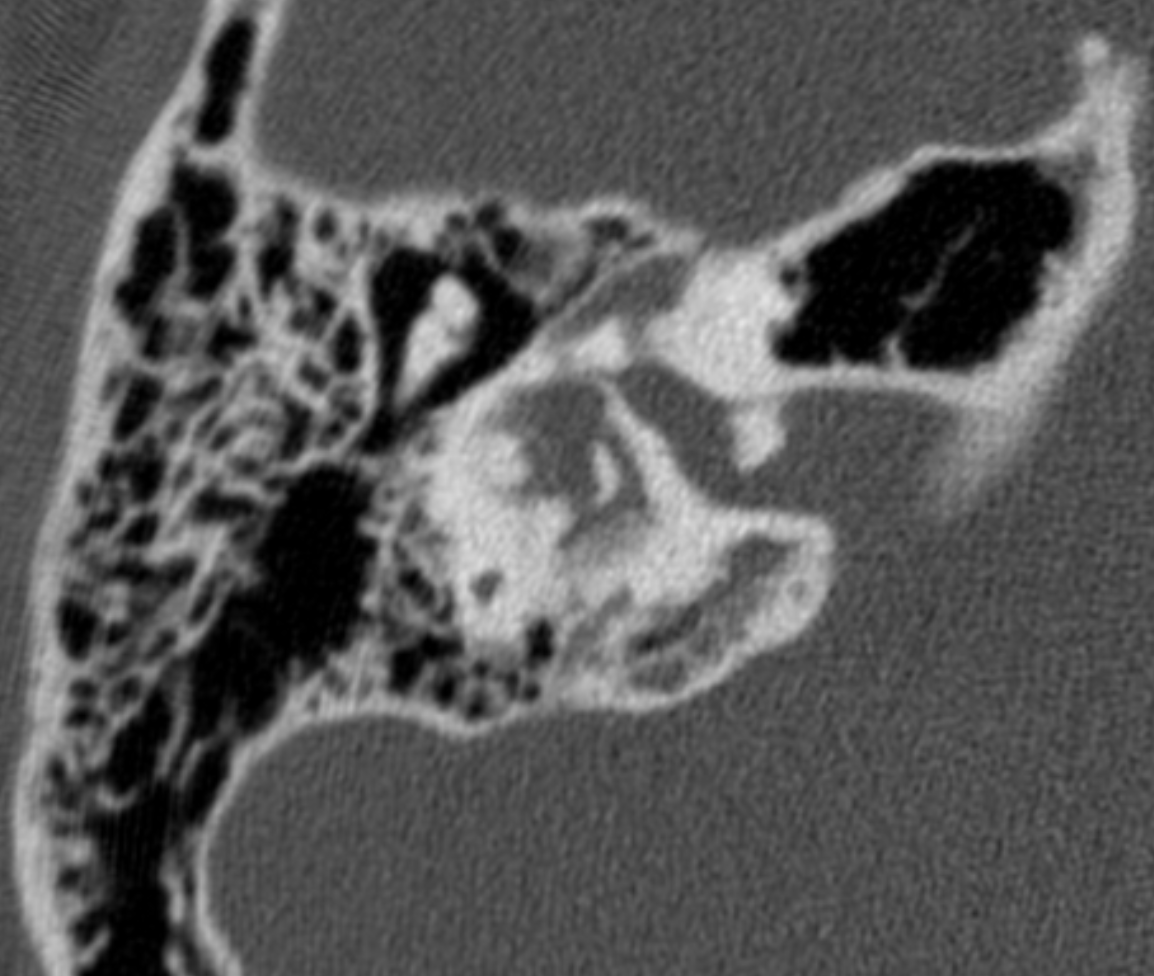

What complication/s are demonstrated here?

Automastoidectomy denotes extensive bone destruction of the mastoid mimicking the appearance of surgery (mastoidectomy), most often caused by cholesteatoma.

Spontaneous evacuation of cholesteatoma can be seen with automastoidectomy 1. In these circumstances, it is often referred to as mural cholesteatoma or unusual cholesteatoma shell, as there is no residual soft tissue mass 2.

Automastoidectomy refers to extensive bony destruction of the mastoid forming one cavity resembling operative mastoidectomy. Cholesteatoma is the most common cause and this subtype is known as “mural cholesteatoma”.

Labyrinthine fistula refers to abnormal communication between inner ear perilymph and middle ear cavity on top of erosion or fracture of the bony labyrinth.